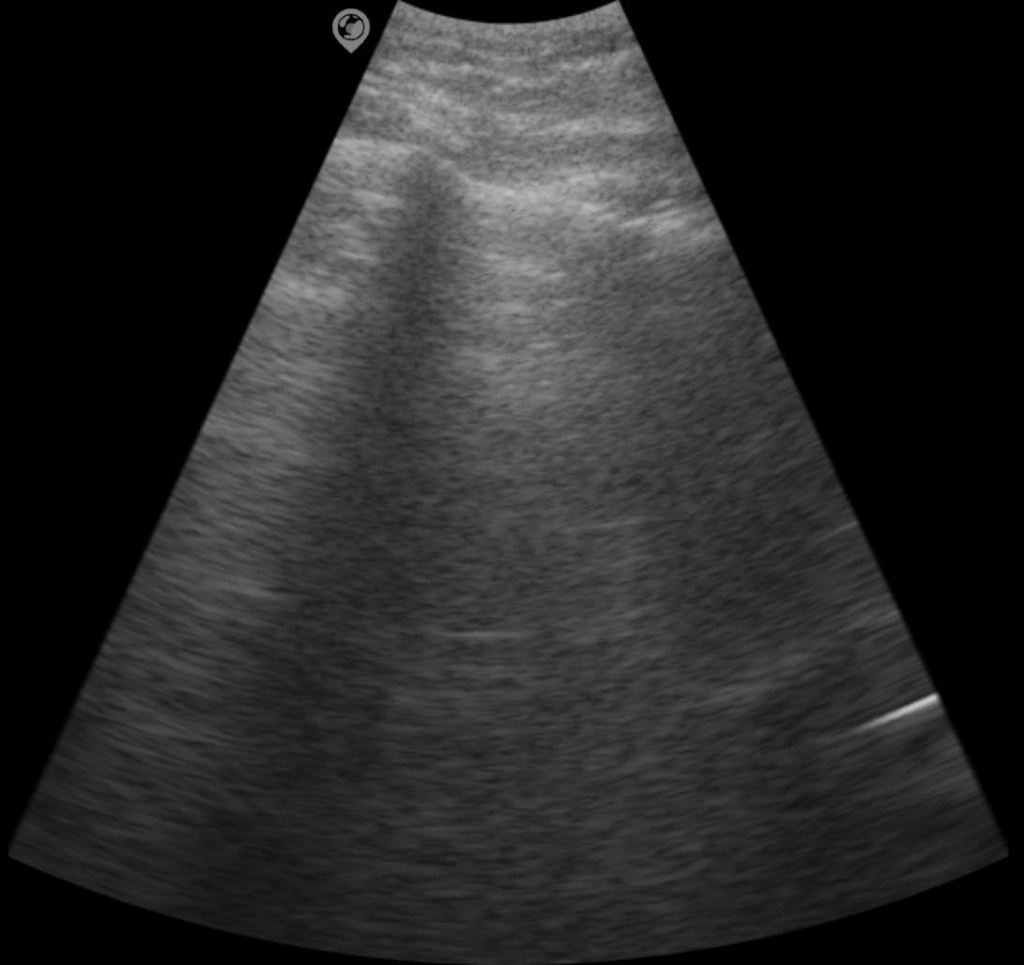

Enhanced posterior echo

When the ultrasonic beam passes through fluid-filled organs or lesions, the resulting attenuation is compensated by excess, leading to enhanced posterior echoes. This phenomenon is commonly observed during the scanning of cysts, bladder, and similar structures.